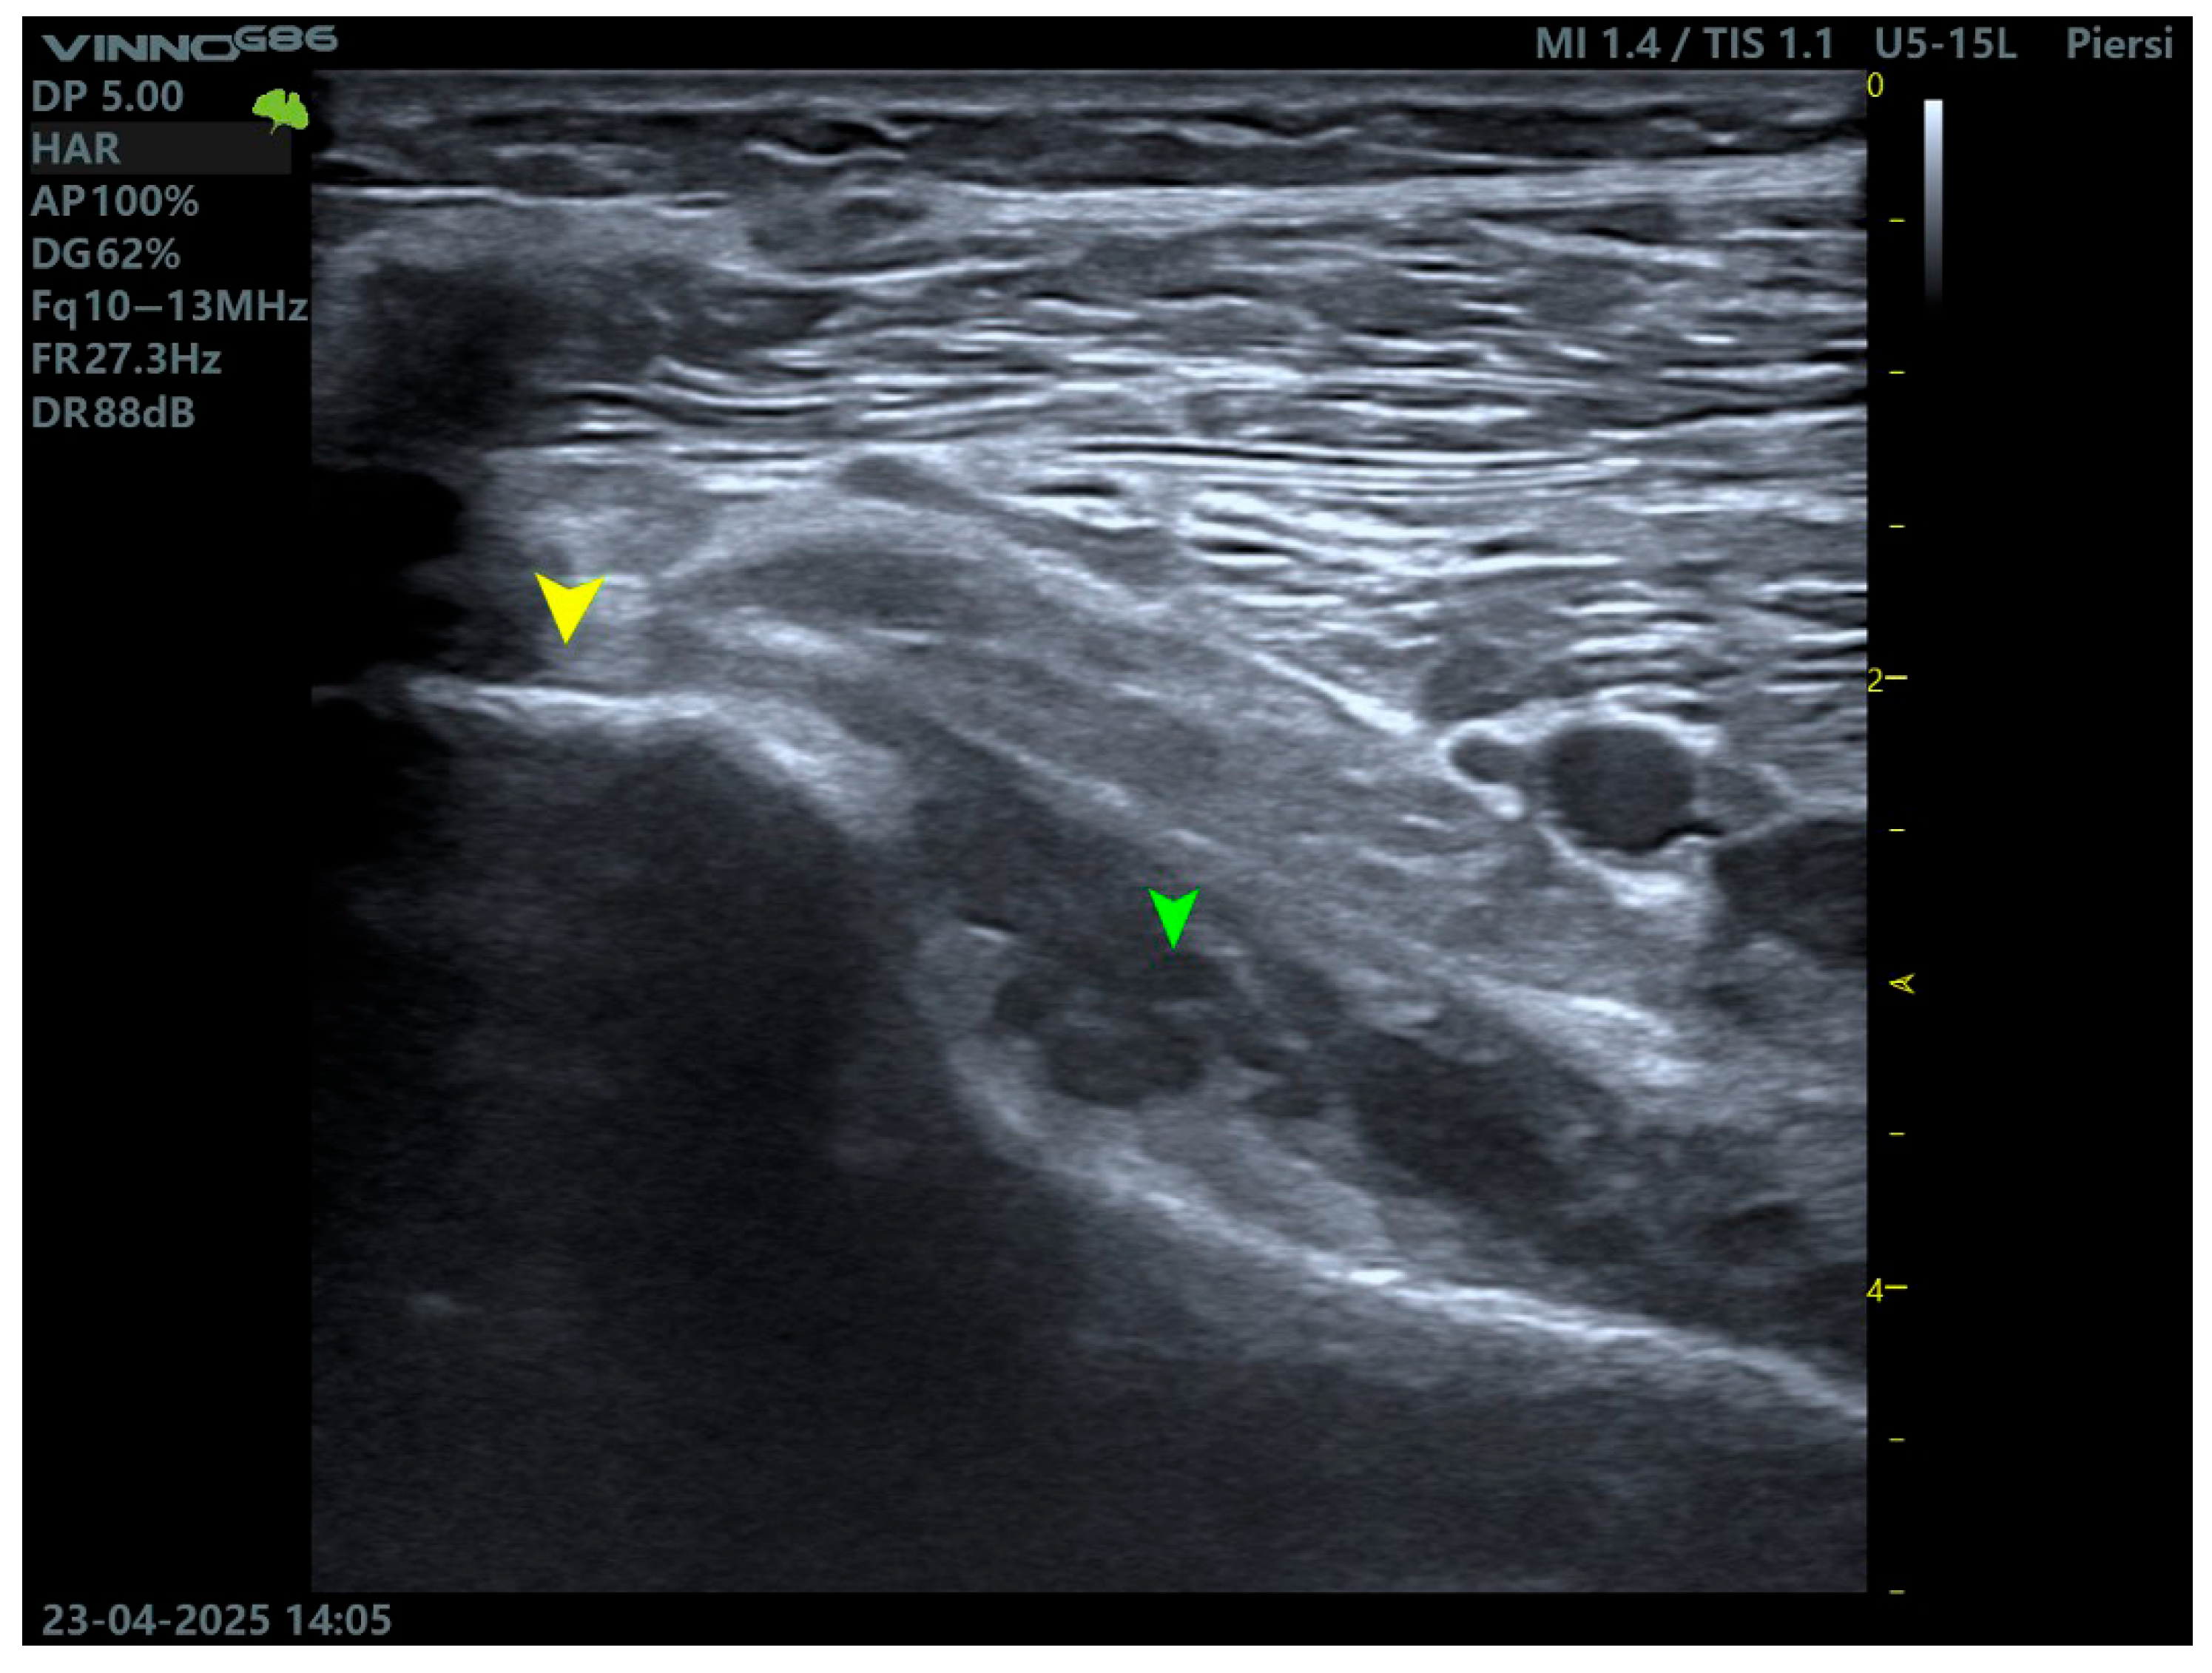

High frequency ultrasonography (≥12 MHz) is gaining relevance as a rapid, dynamic, and non-invasive tool for PT assessment, particularly in outpatient or sports medicine settings [18]. Scanning is performed with the patient in the prone position or with the knee flexed to 30–45°, while applying internal and external tibial rotation. This facilitates the dynamic observation of tendon gliding relative to the adjacent structures and detection of the accessory bands—Figure 3.

Figure 3.

Ultrasound imaging of the popliteus muscle. The yellow arrow indicates the tendon, while the green arrow indicates the muscle belly.

An ultrasound enables the evaluation of tendon echotexture, integrity, calcifications, enthesopathy, and peritendinous fluid collections. It is especially useful in the assessment of lateral knee pain following trauma, particularly in cases where MRI is unavailable or contraindicated (e.g., due to metallic implants) [2].